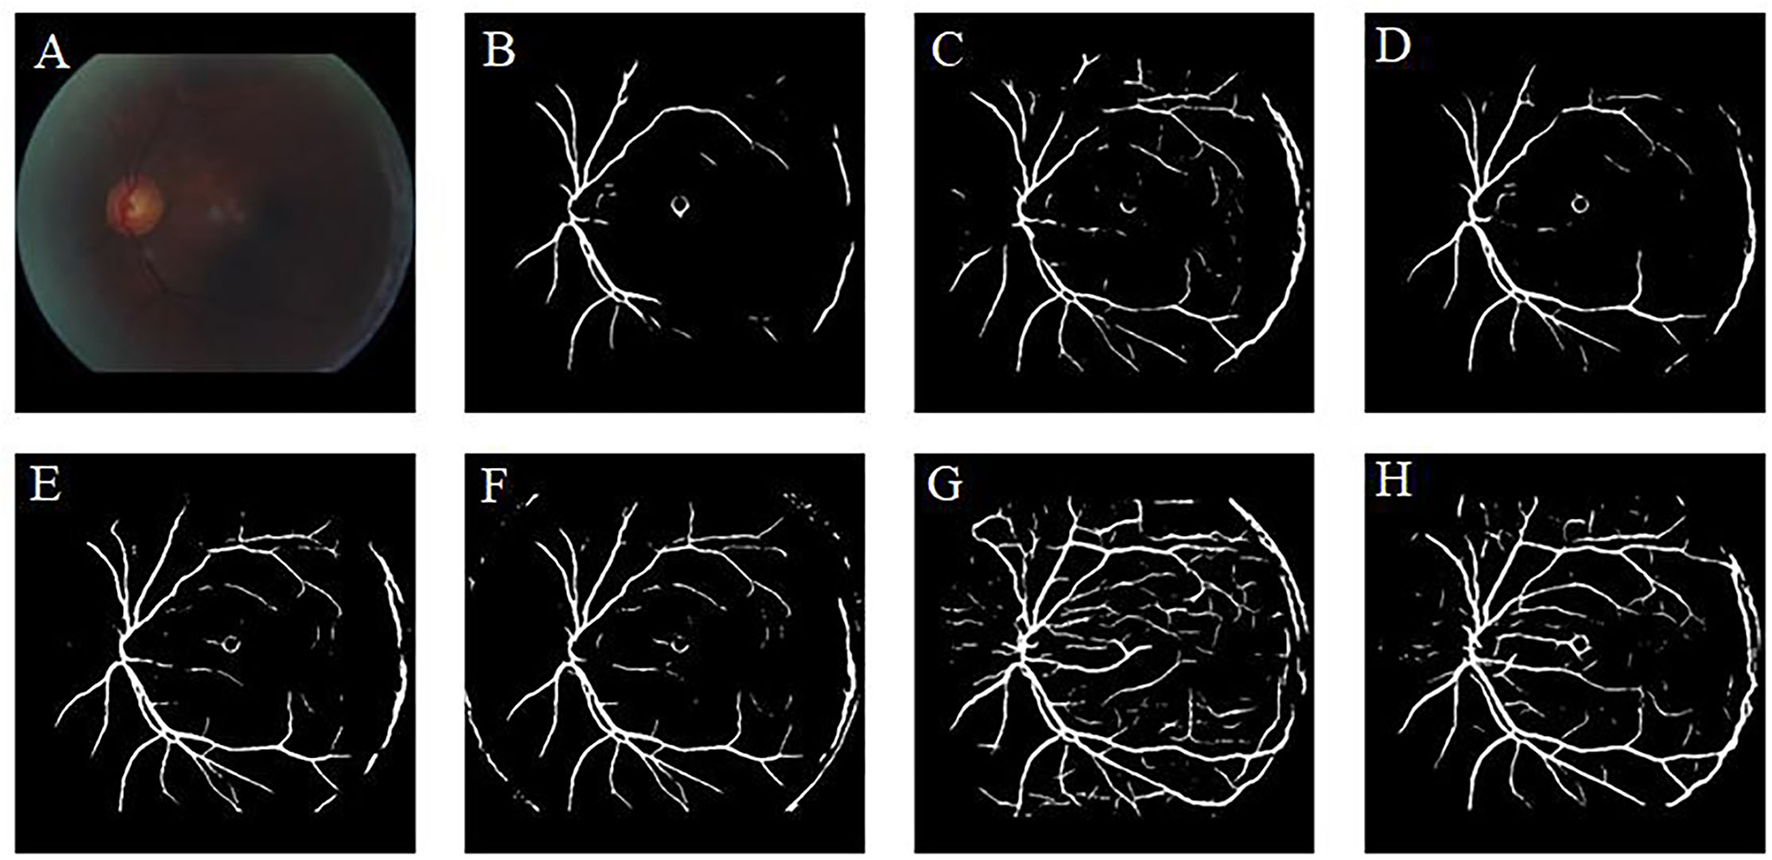

To verify the effectiveness of the CBAM module, we compare the enhancement results of CycleGAN (without CBAM) and Cycle-CBAM (our method) (Figure 9). The first row shows the CycleGAN-enhanced images with zoomed-in views of selected regions (white rectangles). The second row depicts the corresponding images enhanced by Cycle-CBAM. The selected areas mark the ends of blood vessels (the first two columns) or the optic disc (the last two columns). The CycleGAN-enhanced blood vessels (Figures 9A,B) are not distinguishable and fractured, making it difficult for the ophthalmologist to observe the morphology of the endings. At the same position in the same image, the blood vessels enhanced by Cycle-CBAM (Figures 9E,F) are coherent and have clear textures. The optic disc has dense blood vessels and is where the main blood vessels are in confluence. In Figures 9C,D, blood vessels are disconnected at the edge of the optic disc, which does not conform to the continuity of the blood vessels. The intersection of vessels is blurred and cannot be diagnosed. In Figures 9G,H, the edges of the optic disc are easily distinguishable, and the blood vessels are coherent and clear. Cycle-CBAM enhanced images have reddish colors and high saturation.

Figure 9

Visual comparison of enhancement results of CycleGAN and Cycle-CBAM on retinal images. (A–D): Enhanced by CycleGAN. (E–H): Enhanced by Cycle-CBAM.

Our literature review indicates that learning-based methods have been barely explored for the enhancement of retinal images. In this study, a deep learning method was used to enhance various types of low-quality retinal images to improve their quality. Similar to the public dataset, the dataset used in this study contains retinal images taken before and after cataract surgery collected from the clinical work of the research team. This study found that CLAHE improves the overall contrast of the image; however, it thickens the blood vessels. Changes in the original shape of blood vessels may lead to undesirable results in the CAD system. The CLAHE method showed significant differences in the HUE metric from the original image, but visual analysis showed that these differences are caused by the excessive increase of gray information. These images did not receive the votes of fundus doctors in the voting experiment. The p-value of the fusion-based method in the BRISQUE is larger than 0.05 (p = 0.1703), which is significantly different from the original image. However, fusion-based and MSRCP methods improve the image quality by adjusting the illumination, whereas they cannot enhance blurred and high-illumination retinal images. LIME has good enhancement results for uneven-illumination images; however, it produces noise at the junction of foreground and background, which will interfere with the CAD system diagnosis of diseases. Traditional methods cannot restore the color of the images. Our method even succeeds in enhancing the color distortion of retinal images. Figure 9 shows that the introduction of the CBAM module enables the network to have stronger feature extraction capabilities and improves the ability to enhance details, such as tiny blood vessels and optic discs. The extraction of color is also significantly improved, which is crucial for color retinal images. The images enhanced by the proposed method can be segmented into complete blood vessels, exhibiting good performance in the task of segmentation (Figures 12, 13).